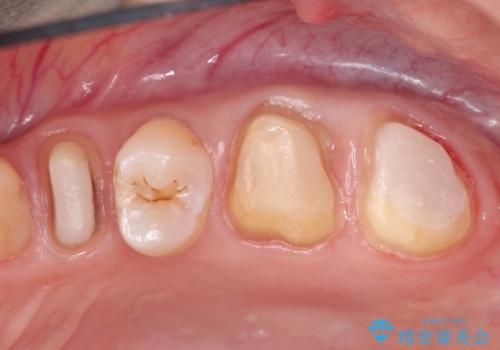

他院による虫歯治療(ドックスベストセメント)の再治療

- 他院でドックスベストセメントによる治療を受けたが、痛みがあり、歯がかけたことを主訴に来院されました。ドックスベストセメントは虫歯を取りきらずに抗菌性のあるセメントを充填し最終修復をする治療法ですが、充填物の中で虫歯が広がる可能性もあります。今回のケースでは特に虫歯を除去できていないため強度が低下し破折を認めました。

当院の治療は虫歯を除去した後、オールセラミッククラウンによる修復治療を行いました。